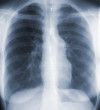

CHRONIC BRONCHITIS AND EMPHYSEMA (COPD)

These 2 diseases of the lungs and the airways are common. They are usually referred to as Chronic Obstructive Pulmonary Disease (COPD), which is a common cause of death. The distinction between COPD and allergic and non-allergic asthma is very important because the treatment for each condition is different.